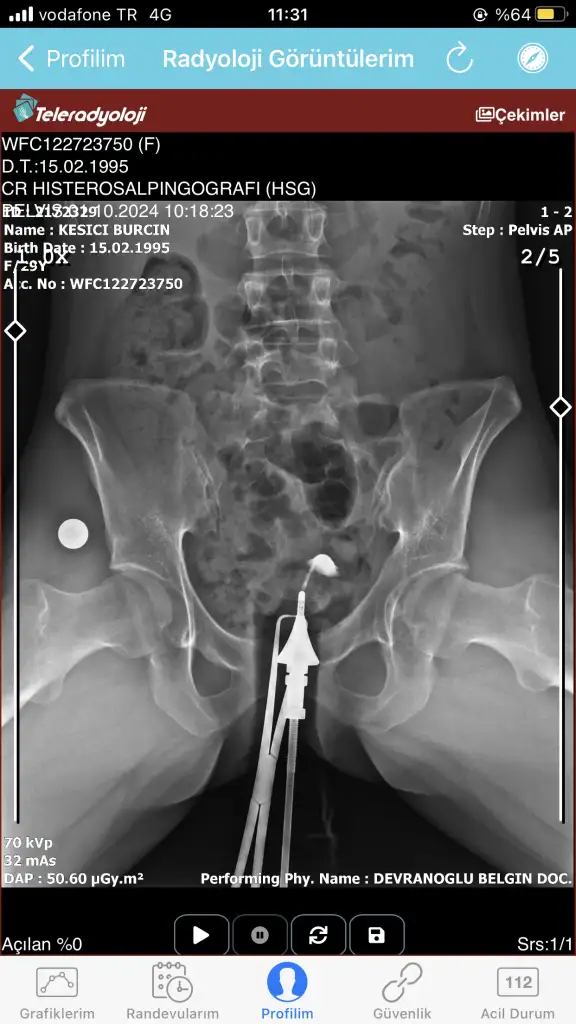

Bugün çekildim doktora gösteremedim daha anlayan yardımcı olabilir mi